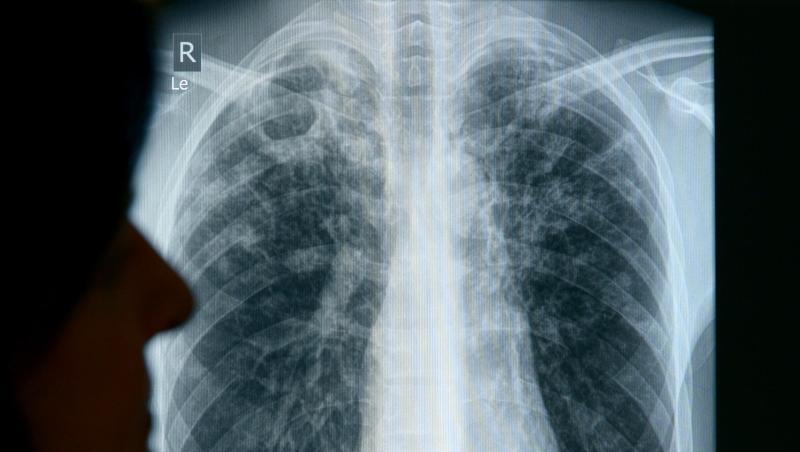

Würzburg (dpa/lby) - Die Infektionskrankheit Tuberkulose ist immer noch nicht ausgerottet. In Bayern haben sich vergangenes Jahr 831 Menschen angesteckt, wie das Landesamt für Gesundheit bekanntgab. Am Sonntag (24. März) ist Welttuberkulosetag. Heuer können die Behörden nur leicht positive Nachrichten vermelden. Mit der Migrantenzahl war die Anzahl der Tuberkulose-Fälle 2015 relativ stark angestiegen. Seitdem sinkt sie, liegt aber noch über dem Niveau früherer Jahre.

Insgesamt gibt es in Deutschland laut Robert Koch-Institut (RKI) jährlich etwa 5500 Fälle, 100 enden tödlich. Infektionen würden häufig zu spät diagnostiziert. "Bei Symptomen wie länger bestehendem Husten, Nachtschweiß, Fieber und Gewichtsabnahme sollte immer auch an Tuberkulose gedacht werden", heißt es vom RKI.